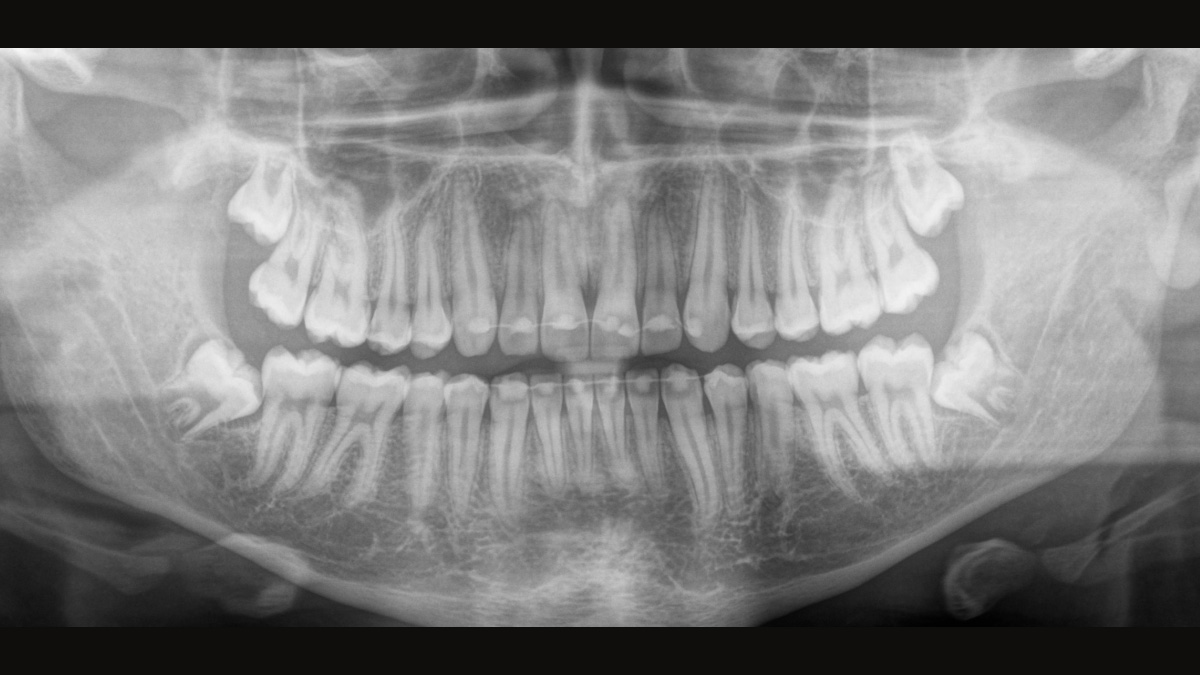

Para obtener imágenes panorámicas excepcionales con alta nitidez. Puede elegir un brazo cefalométrico derecho o izquierdo opcional, que puede reacondicionarse en cualquier momento

El sensor de conversión directa (Direct Conversion Sensor, DCS) ha revolucionado el estándar de la imagen panorámica. Las imágenes radiológicas se convierten directamente en señales eléctricas. Por lo tanto, no hay pérdida de señal debido a conversión de la luz, como es el caso de los sistemas convencionales. El resultado: imágenes con un alto nivel de nitidez y contraste, incluso con una dosis de radiación extremadamente baja. Para obtener información de diagnóstico precisa a fin de apoyar el tratamiento objetivo.

La imagen a continuación muestra una radiografía panorámica con y sin tecnología DCS. Usando la flecha, arrastre el control a través de la imagen para ver la diferencia que el sensor de conversión directa hace con la calidad de la imagen y las posibilidades de diagnóstico.

El enfoque correcto es crucial para excelentes radiografías panorámicas. Con la función de autofoco, usted recibirá automáticamente una imagen con la mejor nitidez posible en foco. Los dispositivos de radiología de Dentsply Sirona toman varios miles de imágenes individuales en un ciclo e identifican automáticamente las áreas donde la mandíbula está posicionada de manera óptima. Luego, sin ningún paso manual adicional, estas imágenes se muestran en una nítida imagen final.